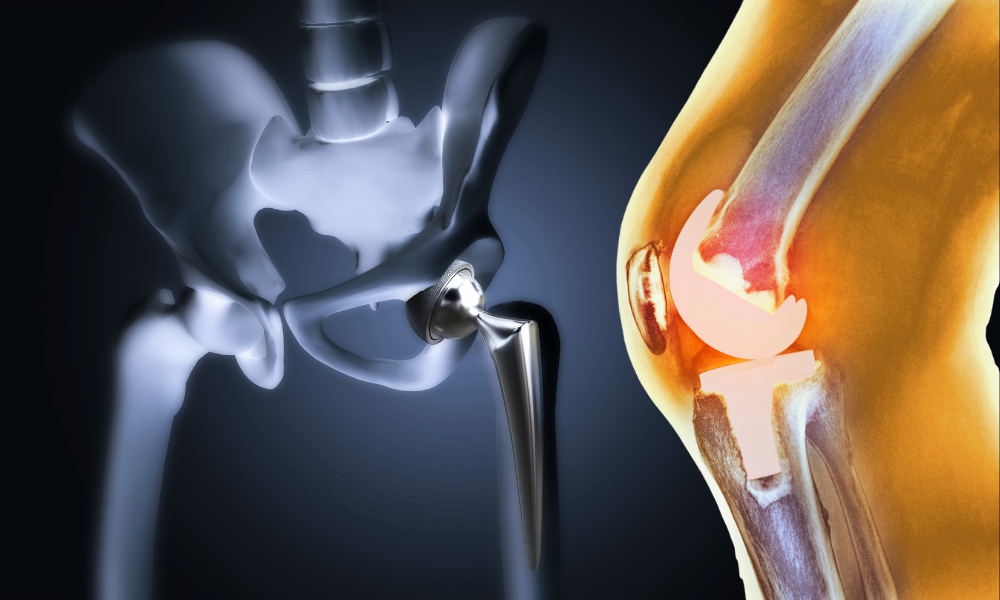

At Dr. Agrawal’s R.K. Hospital, we combine cutting-edge technology with compassionate care to provide the best medical services. Our expert doctors, including specialists in orthopedics, gynecology, and robotic-assisted surgeries, ensure precision treatments and faster recovery.

With 24/7 emergency services, a fully equipped ICU, advanced diagnostics, and modern operation theaters, we prioritize your health and comfort. Whether it’s high-risk pregnancy care, joint replacements, or physiotherapy, we offer comprehensive, patient-centered care under one roof.

Advanced robotic-assisted knee and hip replacement for precise implant positioning, faster recovery, and long-term mobility.

State-of-the-art joint replacement surgeries for enhanced mobility and pain-free movement.